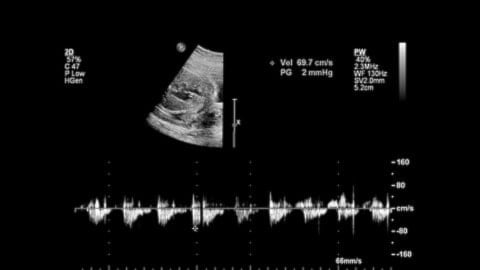

El sistema auditivo de los bebés se desarrolla progresivamente y alcanza una funcionalidad notable alrededor de la semana 23 de gestación.

A partir de este momento, el feto comienza a percibir sonidos, aunque de forma atenuada por el líquido amniótico y los tejidos maternos.